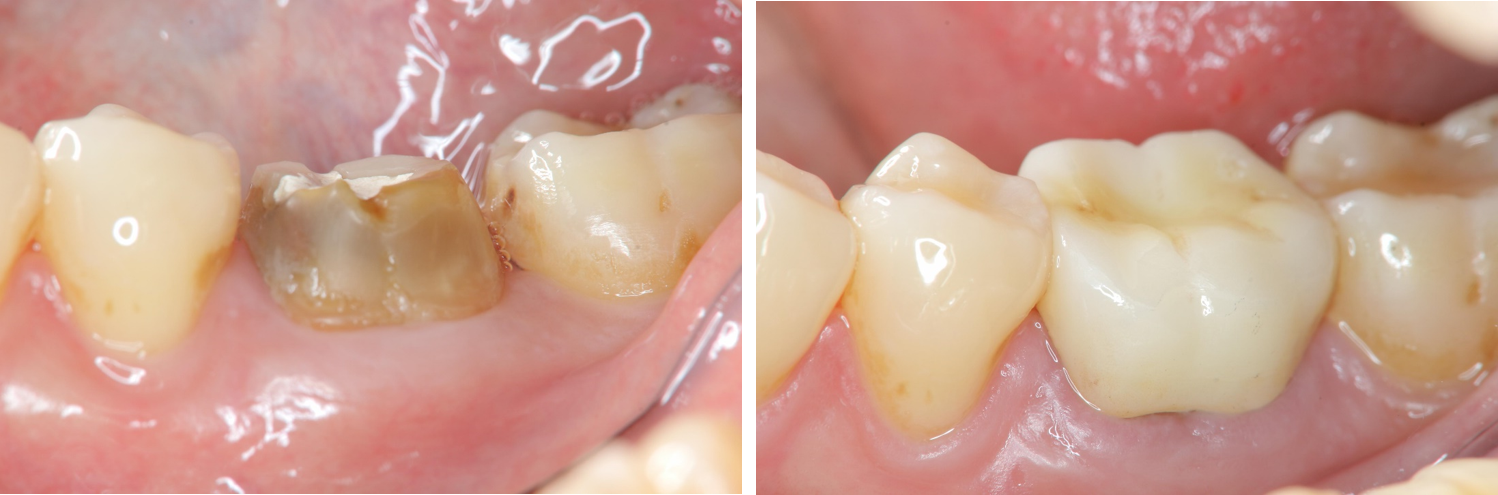

術前、術後比較

治療前,假牙脫落

治療後,口內適應良好